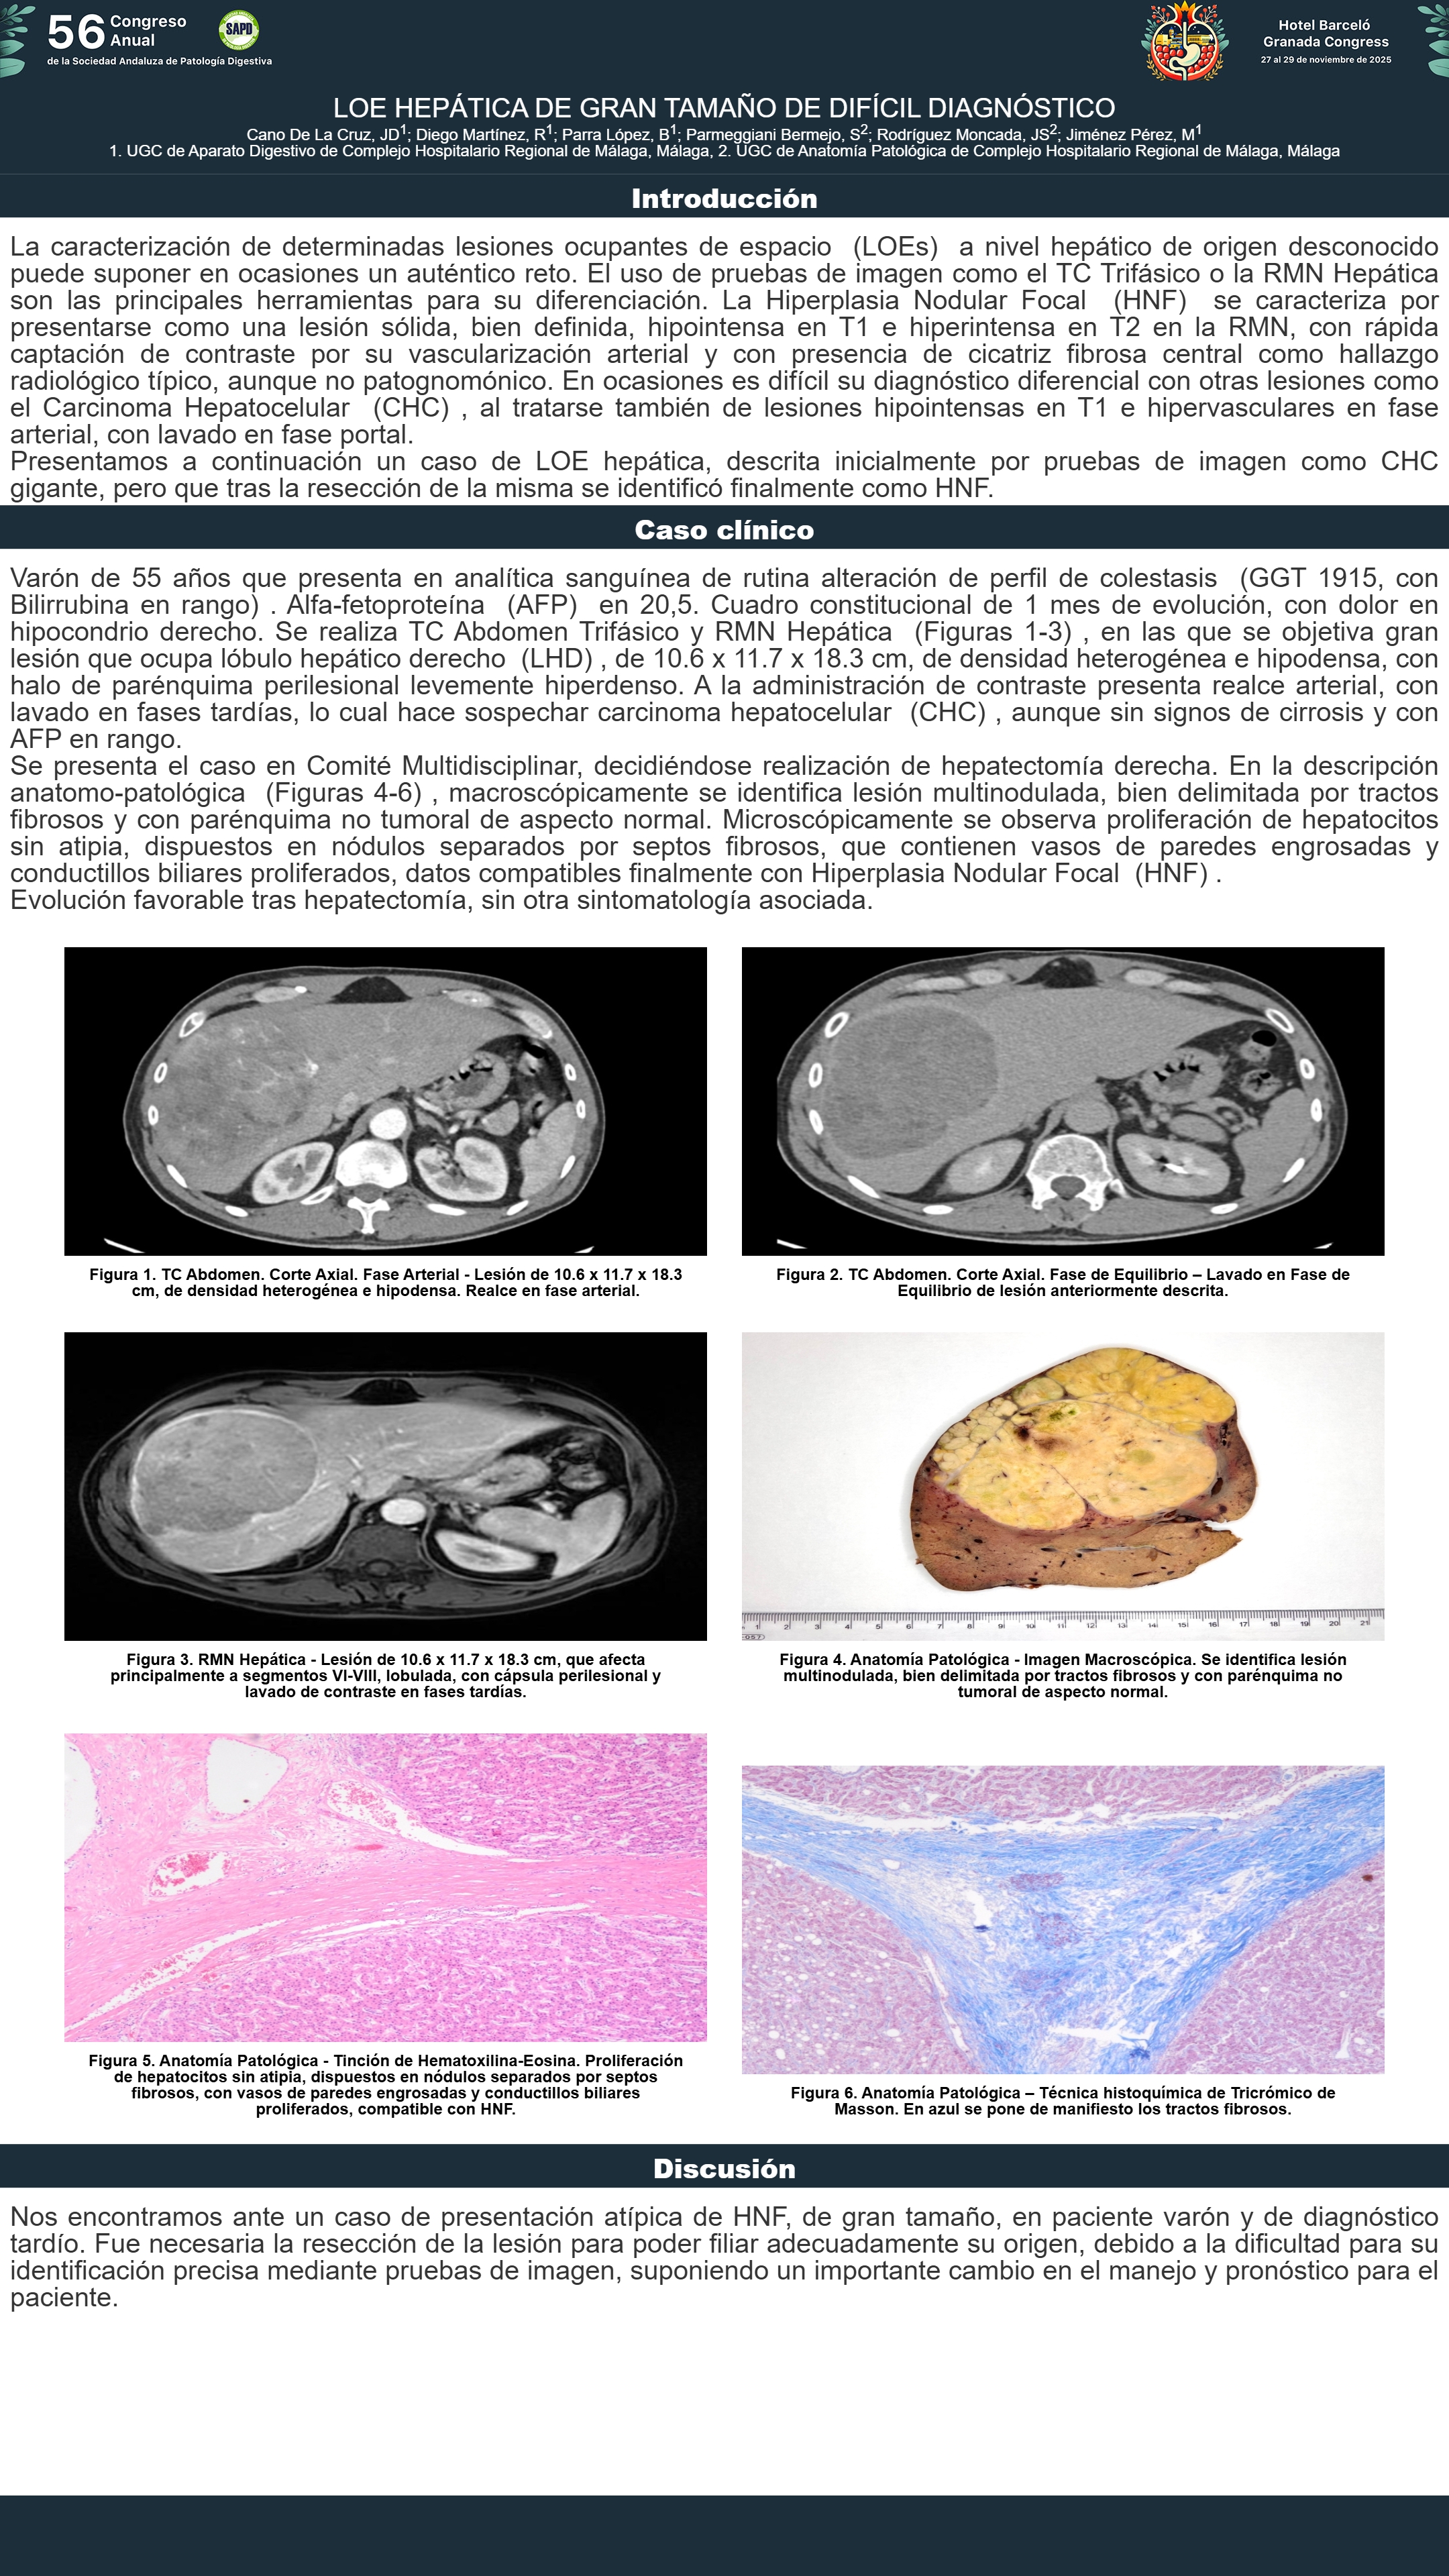

[CP-062] LOE HEPÁTICA DE GRAN TAMAÑO DE DIFÍCIL DIAGNÓSTICO